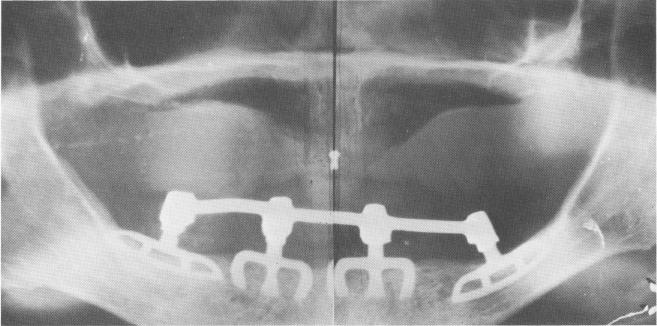

20. Blades are the strongest design to date for the support of a removable prosthesis. If a removable prosthesis is desired, the blades' protruding posts are splinted with a fixed dolder bar, which will serve as a mesostructure (Fig. 11-26) .

1 Four mandibular blades splinted with connecting bar mesostructure